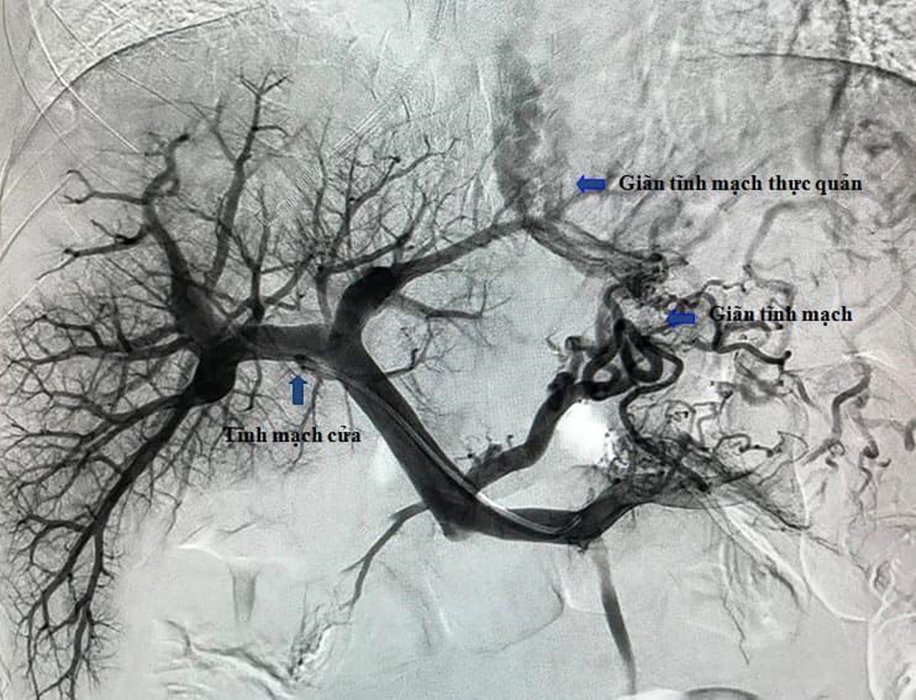

Hình ảnh hệ tĩnh mạch cửa và các búi giãn tĩnh mạch thực quản của bệnh nhân trước can thiệp TIPS. (Ảnh: BVCC)

Để thực hiện kỹ thuật này, bác sĩ sẽ đặt một giá đỡ kim loại có màng phủ trong gan, tạo một dòng chảy trực tiếp từ tĩnh mạch cửa lên tĩnh mạch gan làm giảm áp lực tĩnh mạch cửa, kết hợp với nút các búi giãn tĩnh mạch thực quản để cầm máu.

Lợi ích của phương pháp này là có thể kết hợp với nút búi giãn tĩnh mạch thực quản gây chảy máu (điều này tốt hơn làm TIPS thông thường), can thiệp xâm lấn tối thiểu, tỷ lệ chảy máu tái phát thấp hơn so với điều trị nội khoa và nội soi. Sau phẫu thuật, người bệnh hoàn toàn tỉnh táo.